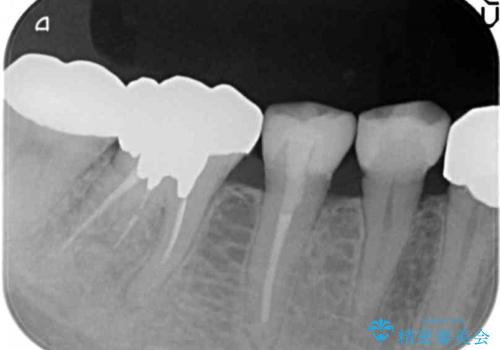

精査したところ、被せ物を入れたばかりの右下の小臼歯(右下5)は不可逆性歯髄炎により神経をとる処置(抜髄)が必要な状態でした。

根管治療後、セラミッククラウンによる補綴治療を行いました。

根管治療により痛みがなくなり、ご安心頂けました。